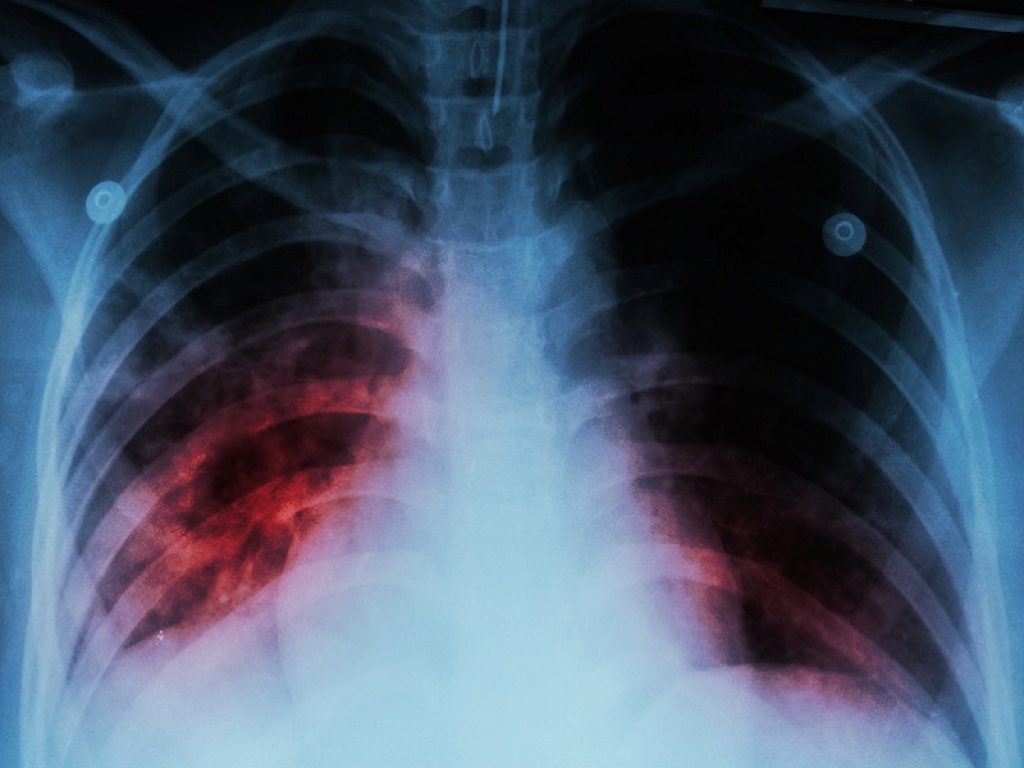

Mesotelioma pleurico maligno: l’associazione di nivolumab più ipilimumab ha determinato un significativo miglioramento della sopravvivenza globale nei pazienti

L’associazione di nivolumab più ipilimumab ha determinato un significativo miglioramento della sopravvivenza globale (OS) in pazienti con mesotelioma pleurico maligno (MPM) non trattato in precedenza e non resecabile. L’importante annuncio arriva dai dati dello studio clinico di fase 3 CheckMate -743, uno dei tre trial presentati durante il Simposio Presidenziale della Conferenza Mondiale 2020 sul Cancro del Polmone.